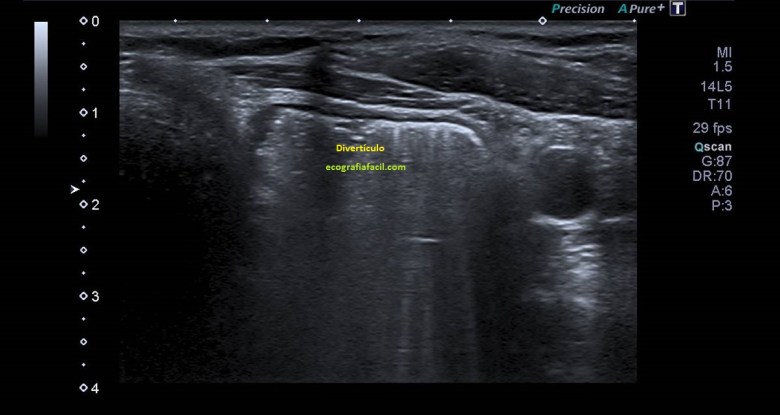

Comenzamos el estudio para visualizar la glándula tiroides de una forma global, como puedes ver en la imagen 1.

En la imagen 2, al lado de la zona donde visualizamos normalmente el esófago se observa una imagen más grande, no tan circular y con gas en su interior. Es de un tamaño considerable, heterogénea por el gas interno. Es una imagen anormal que requiere evaluación del radiólogo.

1